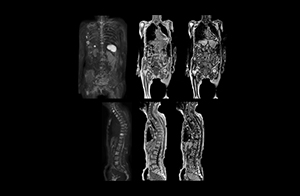

“When we limited the scan coverage to the area from neck to femur, we could fit more clinical information in approximately the same scan time. So, we added coronal mDIXON, sagittal T1-weighted, and sagittal STIR sequences to our examination, instead of performing only axial DWIBS and coronal single-shot TSE scans.” The single shot T2-weighted TSE images are used for morphology and compared to DWIBS images to identify T2 shine-through. Sagittal STIR images are used in patients with inflammation or bone metastasis.

“Switching to coronal DWIBS – rather than axial – further shortens scan time,” says Mr. Naka. “Important is that a dS SENSE factor of 5 shortens exam time while high image quality can be maintained, thanks to Ingenia’s dStream architecture.” He adds that the coronal orientation also avoids artifacts that are specific to combining axial images.

“When we use a coronal DWIBS acquisition, we can perform a full whole body examination, including other required sequences, within 30 minutes,” he says.

Kawasaki Sawai Hospital’s whole body protocol also includes an mDIXON FFE sequence. Because mDIXON provides images for four contrast types – water only, fat only, in-phase and out-of-phase – from a single acquisition, it is useful in many ways.